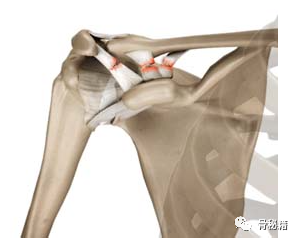

肩锁关节是肩部的重要组成部分;它将骨骼与上肢连接起来。该关节是锁骨和肩峰之间的平面关节,包含易于退化的半月板状纤维盘。肩锁关节囊和韧带在水平方向稳定关节,而喙锁韧带复合体提供垂直稳定性。在锁骨和肩胛骨运动期间,三角肌和斜方肌提供动态稳定性。

韧带形成一个倒三角形,其顶点位于喙突,其基部位于锁骨远端三分之一的下表面。喙肩韧带是三角形的纤维结构,从喙突外侧延伸到肩峰上。尽管它的一些纤维与下 AC 囊重叠,但该韧带并不是重要的关节稳定器 。CC 韧带由梯形韧带和圆锥韧带组成,是 AC 关节的主要垂直稳定器,当关节囊破裂时替代其主要的水平稳定器。圆锥韧带和梯形韧带在解剖学和功能上是不同的。梯形韧带较大,大致呈四边形,沿着梯形线(梯形脊)插入锁骨远端,跨越距关节线 1.5-3.0 厘米的区域。圆锥韧带呈圆锥形,几乎垂直,位于梯形韧带的后内侧。它的纤维在向上延伸以插入圆锥结节和相邻的锁骨时会扭曲,跨越关节线内侧 3-5 厘米 。梯形韧带抑制锁骨后移位和 AC 压缩,而圆锥韧带主要负责垂直稳定性,抑制锁骨的上移 。